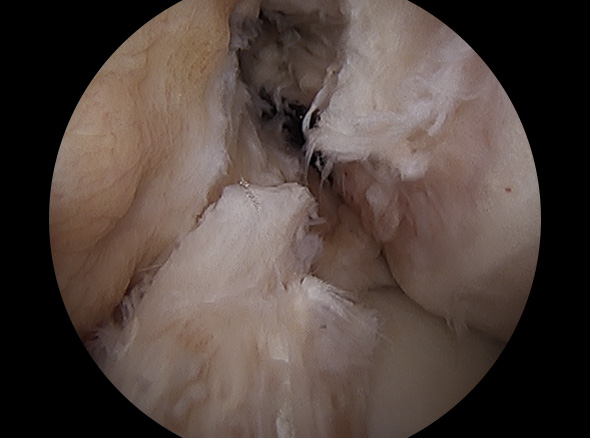

이식한 인대 고정